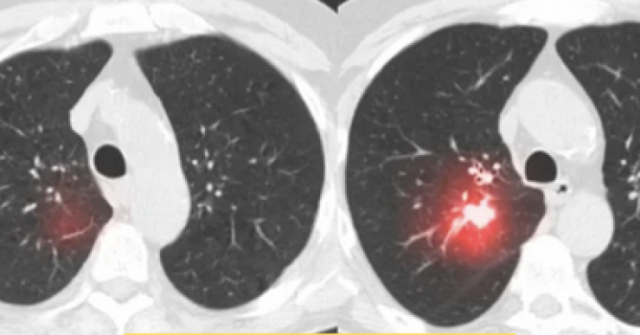

Chuyên gia chỉ điểm thảo dược hỗ trợ giảm các triệu chứng đàm ho

Chia sẻ cùng những vất vả của bệnh nhân phổi tắc nghẽn mạn tính COPD, chúng tôi kết nối bác Sến cùng Ths. Bs Lê Trung Nam, ĐH Y Dược Tp Hồ Chí Minh. Nắm được tình hình bệnh của bác Sến, Ths. Bs Lê Trung Nam đưa ra giải thích rất chi tiết: “Bệnh Phổi tắc nghẽn mạn tính COPD là bệnh hô hấp mạn tính đặc trưng bởi sự hạn chế luồng khí thở ra không phục hồi hoàn toàn khiến bệnh nhân thường xuyên Đàm ho, khó thở. Ban đầu bệnh nhân khó thở khi gắng sức, nếu không điều trị tốt sẽ chuyển nặng, khó thở ngay cả khi nghỉ ngơi.”